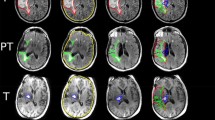

There were differences between the different molecular groups (IDH mutated/1p19q co-deleted vs IDH mutated vs IDH wild-type) when it came to the distance from SVZ to tumor, but only when measured from tumor center (p = 0.033, median distance 20.7 mm vs 16.5 mm vs 14.8 mm) and not from tumor border (p = 0.797, median distance was 0 mm for all groups) (Fig. 2a). There were also differences between molecular groups when it came to distance to the SGZ, both from tumor center (p < 0.001, median distance 42.3 mm vs 31.4 mm vs 20.8 mm) and from tumor border (p = 0.007, median distances 15.4 mm vs 3.8 mm vs 0 mm) (Fig. 2b).

a Shortest distance in millimeters from the tumor border to the subventricular zone (SVZ) for the different groups of low-grade gliomas. b Shortest distance in millimeters from the tumor border to the subgranular zone (SGZ) for the different groups of low-grade gliomas. c Shortest distance in millimeters from the tumor border to the subventricular zone (SVZ) for different groups of IDH mutation status. d Shortest distance in millimeters from tumor border to the subgranular zone (SGZ) for different groups of IDH mutation status

Tumors with IDH mutation and 1p19q co-deletion showed similar distances from both SVZ and SGZ as the tumors with IDH mutation and no co-deletion. When analyzed for IDH mutation status alone (IDH mutated vs IDH wild-type) we found no differences when it came to distance to the SVZ from neither the tumor center (p = 0.055, median distance 18.7 mm vs 14.9 mm) nor tumor border (p = 0.752, median distance was 0 mm for both groups) (Fig. 2c). There were differences between the IDH mutated and IDH wild-type gliomas with respect to the SGZ, both when measured from tumor center (p < 0.001, median distance 35.7 mm vs 20.8 mm) and tumor border (p = 0.006, median distance 7.7 mm vs 0 mm) (Fig. 2d).